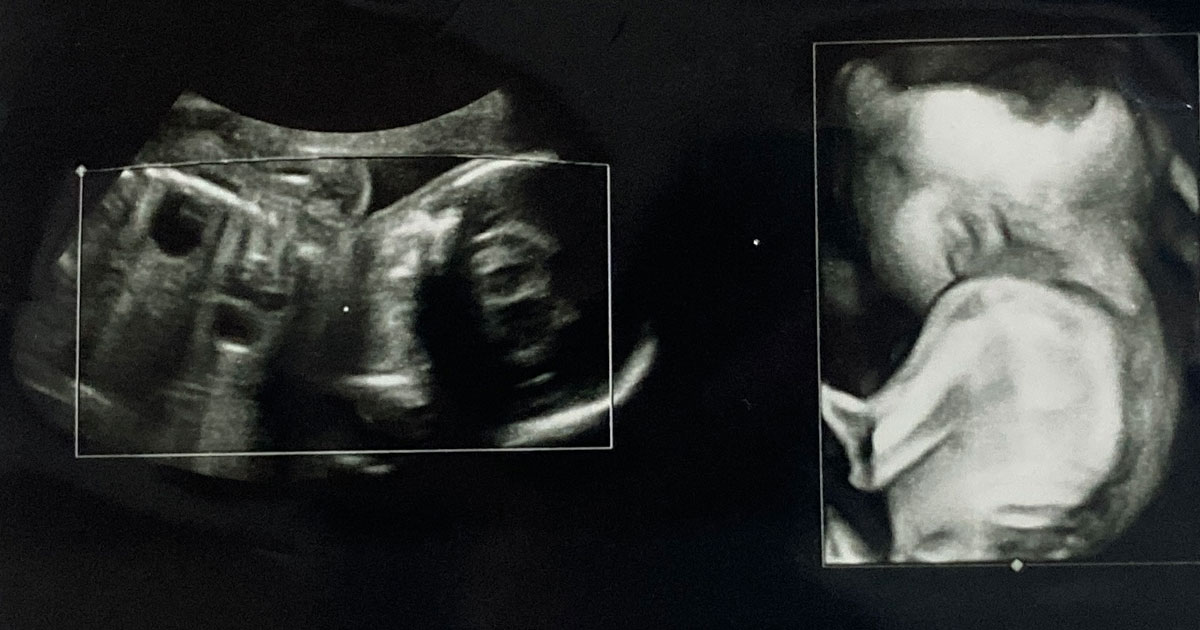

- 超音波:超音波または超音波検査は、子宮内の胎児の写真を撮影する画像処理の一種です。医師は、超音波を使用して、開いた脊椎などの二分脊椎の兆候を頻繁に確認できます。